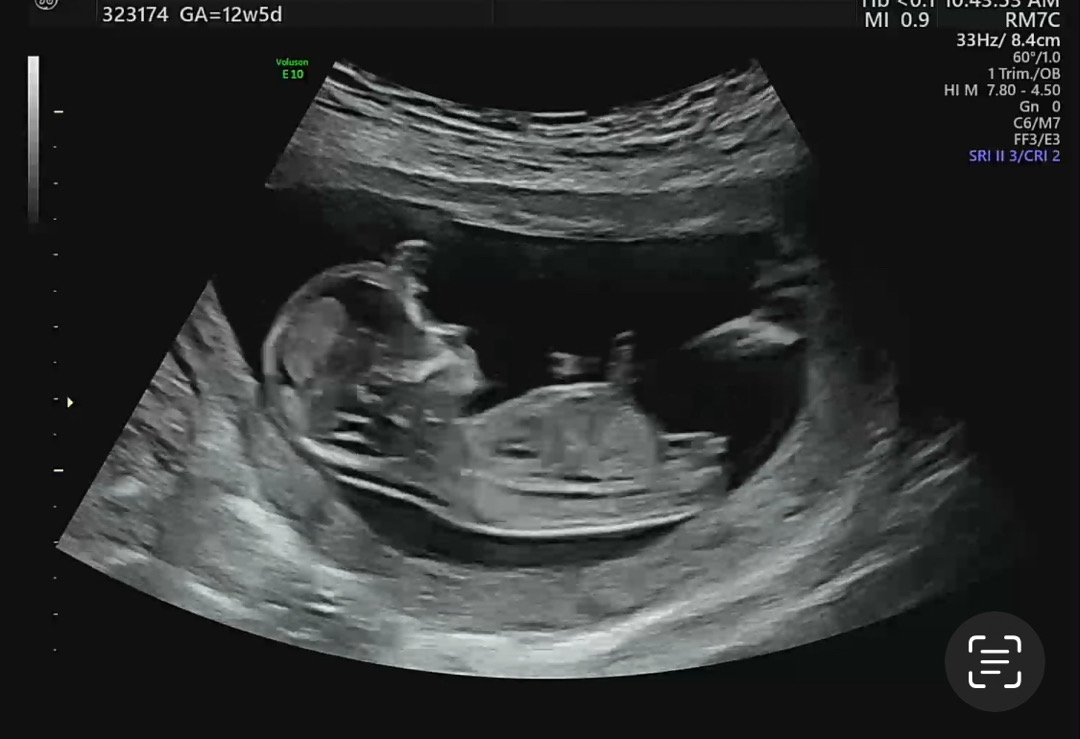

저희는 셋째예용! 아들 둘, 오늘 12주5일인데, 담당쌤이 다리사이 봐주셨어요. 성별봐주신다고. 여태 아들 촘파에서 못봤던 갈라짐인데... 같은 주수에 이런 촘파 찾기 힘드네요 ㅠㅠ 우리 딸과 비슷하다 하시는분 계실까요?